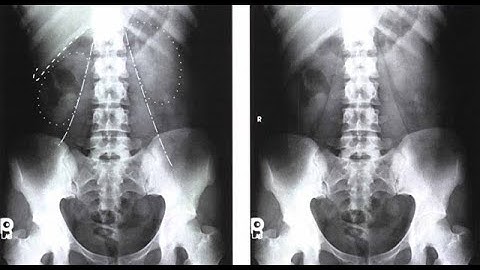

How to Position for Routine Abdomen X-Ray Projections